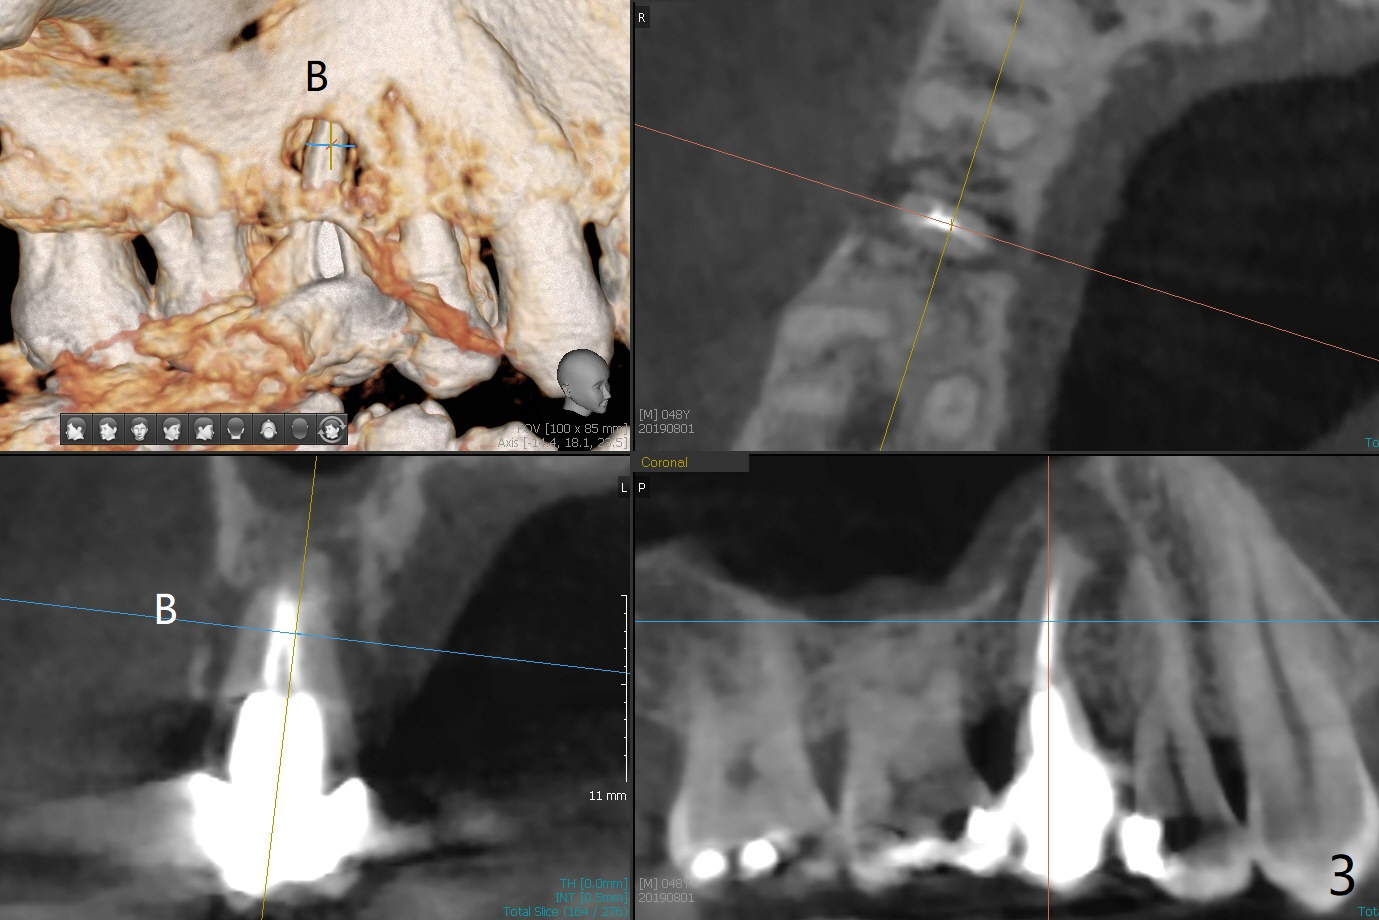

A 48-year-old man has had palatal and buccal abscesses at #4 for 6 and 1 months, respectively (Fig.1). The patient loves bubble gums. There is a post at #4 (Fig.2). CBCT shows apical buccal and palatal defects (Fig.3,4). There are no deep periodontal pockets. The tooth has mobility II. No guide is fabricated so that we have options to do bone graft or immediate implant after extraction, depending on extent of bone defects. Later impression is taken for guide. Use UF implant 4.5x10 mm with sinus lift (PRF membranesx2).